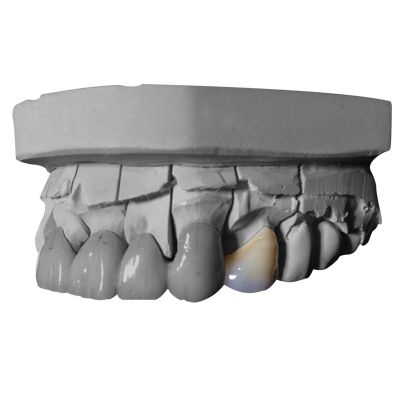

■ CASE007 上顎四番 メタルボンド(MB)

上顎四番 メタルボンド(MB) クラスプがかかるように鉤歯設定してあります。

上顎四番 メタルボンド(MB) クラスプがかかるように鉤歯設定してあります。